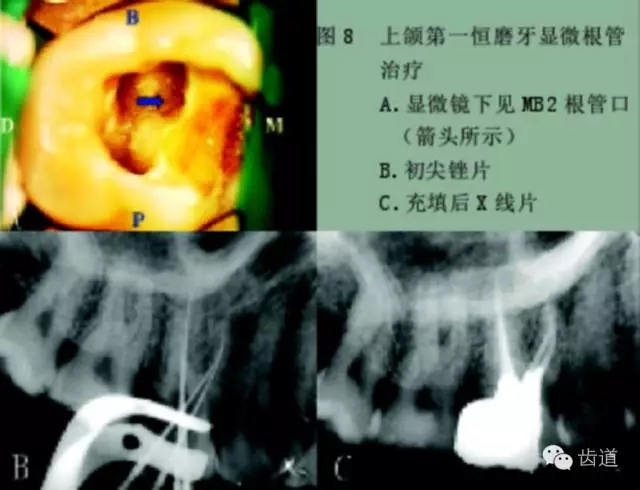

手術(shù)顯微鏡是用于尋找隱藏或遺漏的根管最重要的工具。因?yàn)槭中g(shù)顯微鏡能夠幫助醫(yī)生觀察到肉眼或普通放大鏡無法分辨的根管口和微小病損。在手術(shù)顯微鏡下,利用高倍數(shù)(16~24倍)的放大作用以及理想的照明條件,仔細(xì)檢查患牙的髓室底,許多細(xì)微的解剖結(jié)構(gòu)能容易被發(fā)現(xiàn)。

為了光線能充分進(jìn)入髓腔,髓室頂應(yīng)完全揭去,開髓口的形態(tài)應(yīng)根據(jù)具體牙位進(jìn)行適當(dāng)修改,使得所有根管口都能夠充分暴露。同時(shí),對(duì)髓底進(jìn)行美藍(lán)染色也有助于根管口和微小病損的識(shí)別。